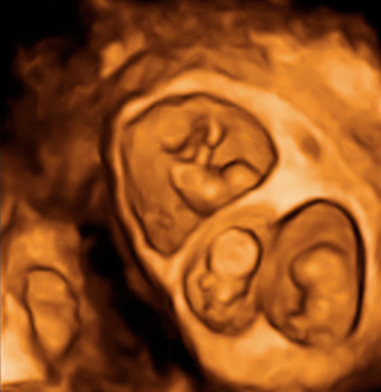

Ecografía 2D y 3D de la semana 12: embarazo de trillizos

Vemos tres planos de un embarazo de trillizos en ecografía 2D en diferentes cortes de imagen. Lo que vemos en 3D es lo que los ecografistas conocen como "un queso", es decir el embarazo visto en tres dimensiones desde una perspectiva determinada. Lo que realmente esconde ese peculiar queso es un embarazo de trillizos: un feto independiente, separado de sus hermanos por una membrana.

Los gemelos se desarrollan en dos bolsas diferentes. En otro corte de la imagen, se ve un embrión independiente separado por una membrana de los otros dos hermanos, que se sitúan en bolsas independientes.